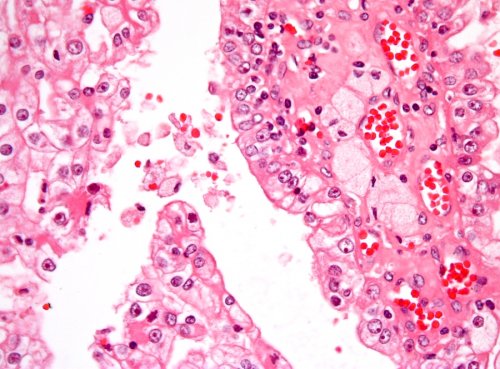

Falls notwendig wird auch eine Biopsie gemacht, indem mit einer Nadel Zellen oder Gewebe entommen werden, um diese mikroskopisch zu untersuchen.